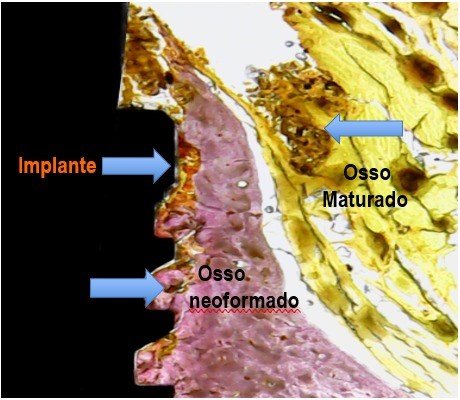

Porém, após a instalação do implante, não tínhamos como acompanhar e medir o aumento do contato entre osso e implante (BIC), durante as diferentes fases da cicatrização e remodelamento ósseo. A única forma de obtermos essa medida de BIC é através de cortes histológicos, como demonstrado na figura 2.